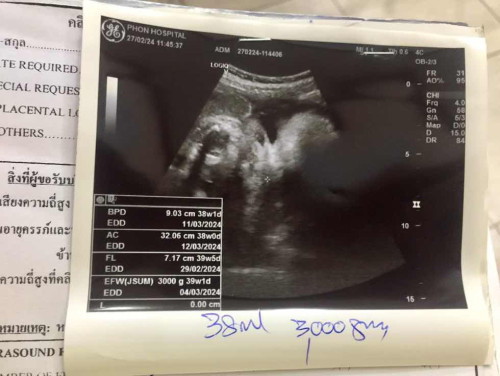

อายุครรภ์38+2กำหนอดคลอด 10มีนาคม

อายุ ครรภ์ 38+2 น้ำหนักน้องได้ 3,000กรัม. น้อยไปไหมคะ แม่ท้องเล็ก. ท้องไม่ค่อยใหญ่ กำหนอดคลอด 10 มีนาคม แม่ๆ กำหนดคลอดวันไหนบ้างคะน้องน้ำหนักเท่าไหร่